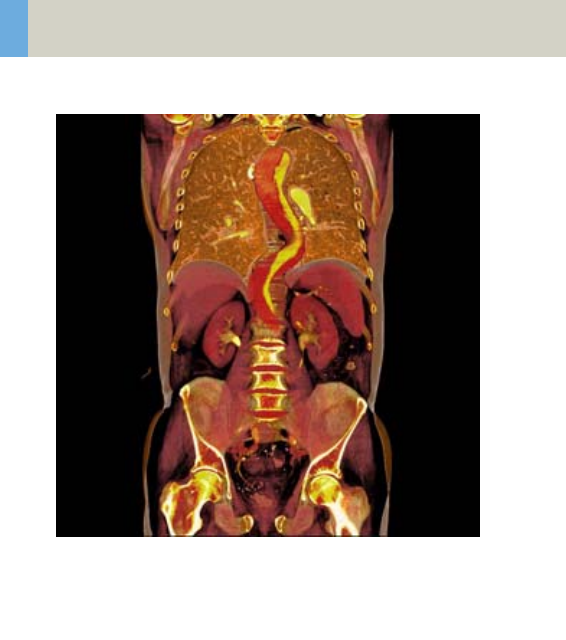

- WholeBodyAngio 414